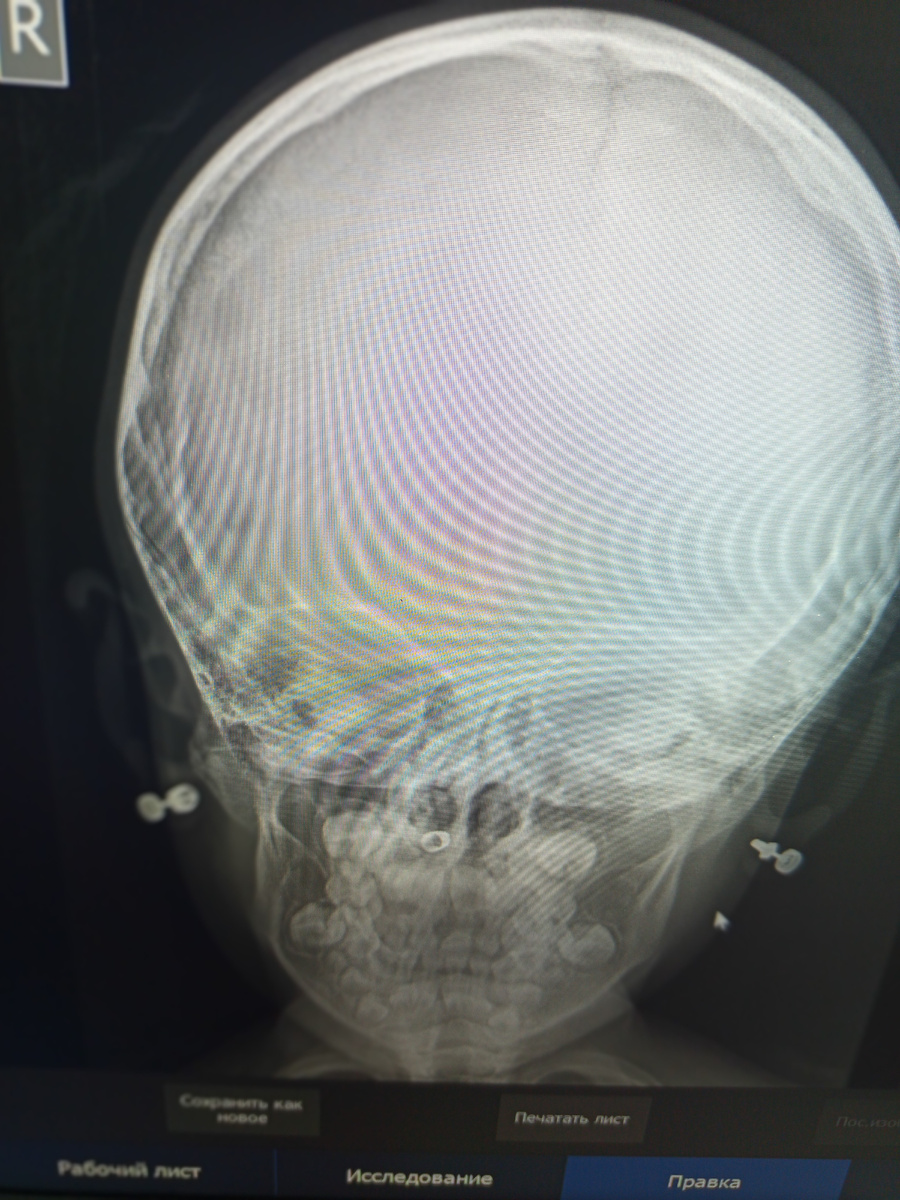

Привели ребенка , 5 лет, на снимок черепа.

–С какой стороны ребенок ударился головой?

–Она не разговаривает , но показывает правую сторону , –поясняет родительница.

Проявляю прямой снимок:

На голове я видела , что ни резинок , ни заколок не было

–Что у нее в области носа?

–А что у нее там?

–Не знаю , какая-то металлическая штучка?

какая металлическая штучка??? –У мамы сильно округлились глаза.

–Она ничего в носик не могла засунуть?

–Не знаю , у нас РАС, вы же видите , что она не разговаривает.

–Ладно , идите к врачу, там разберутся.

Разбираться не с чем , больница у нас не детская, это нужно теперь со снимком ехать в детскую больницу , чтобы вынуть инородное тело.